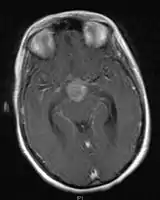

- Mainly located in midline structures, suprasellar region or pineal gland, also basal ganglia and hypothalamus

- Pineal Gland Germinoma

- Suprasellar Germinoma